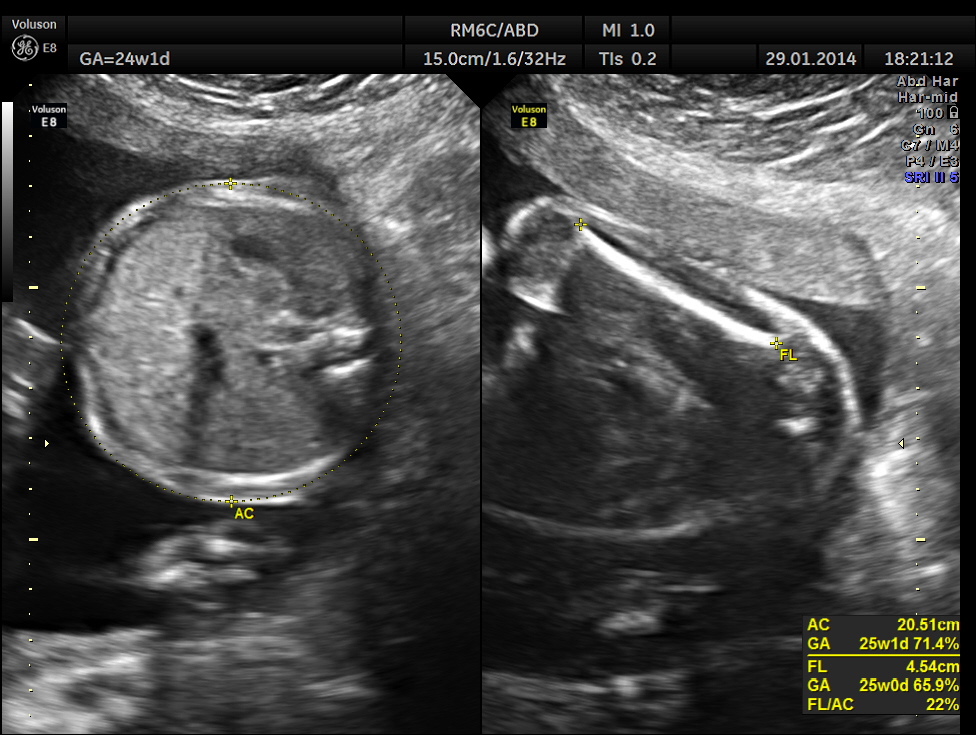

Images of the other organs are given below.